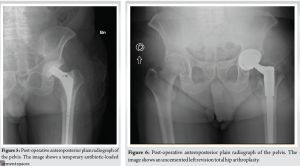

In January 2021, the patient presented with groin and buttock pain at rest and during walking, with limited range of motion (R.O.M) but with no symptoms of inflammation. MRI examination showed the presence of a voluminous three-lobed fluid-filled cyst around the implant (Fig. 3). Synovial fluid was aspirated (23 ml) and four samples were collected for cultures, all of them yielding negative results. In February 2021, the patient underwent arthroscopic synovectomy. After 1 month of follow-up, he underwent a new MRI, which showed the presence of a new voluminous cyst around the implant surrounding the nervous-vascular bundle causing paresthesia on the medial side of the thigh, and showed the same characteristics as the previous one. Subsequently, he was admitted to the hospital and a complete open resection was performed with femoral and obturator nerves neurolysis. Several samples were collected for cultures, all of them yielding negative results. The patient presented good hip function, but complained of persistent groin pain. After 7 months, he underwent 111 Indium-labeled white blood cell bone scan which documented a high leukocyte uptake around the greater trochanter. In October 2021, he underwent a new ultrasound which showed the presence of a new voluminous cyst (50 mm × 15 mm) around the implant with the same characteristics as the previous one. Synovial fluid was aspirated (20 ml) and sent for cultures. Cultures were negative. In November 2021, he was admitted for further examinations. PET-CT showed presence of increased uptake around the ileo-psoas and vastus lateralis muscles. A new ultrasound showed the presence of a voluminous cyst (42 mm × 10 mm) around the implant, and blood test revealed ESR of 42 mm, and C-reactive protein (CRP) level of 0.58 mg/dl. In January 2023, he underwent triple phase bone scan that showed increased activity isolated to the proximal femur around the femoral stem. Since there were no clear signs of infection, an isolated single stage femoral stem revision was performed in February 2023. During the surgery, several swabs were collected and sent for culture. All three samples came positive for S. caprae. As per infectious disease consultant’s recommendations, the patient was treated with 100 mg oral minocycline twice a day for 4 weeks. Two months after surgery, the patient complained of groin and buttock pain. Inflammatory markers were elevated (CRP 47.30 mg/dL), and a pelvis MRI showed a fluid containing formation with the same characteristics as the previous MRI (Fig. 4). In June 2023, he underwent a new ultrasound which showed the presence of a new voluminous cyst around the implant with the same characteristics as the previous one. Synovial fluid was aspirated (18 ml) and sent for cultures. Cultures revealed the presence of S. caprae; susceptibility to rifampin and minocycline was confirmed, which prompted the infectious disease consultant to initiate these antibiotics. The patient started taking 100 mg oral minocycline twice a day and 600 mg oral rifampin once a day. At this time, the decision was made to opt for the two-stage revision prosthesis.

In July 2023, he underwent explant and spacer placement. During the operation, synovial and tissue samples were collected for cultures that were positive for the same pathogen. The femoral stem and acetabular component were removed, and thorough debridement and irrigation with pulse lavage were performed. Vancomycin-Gentamicin loaded bone cement was used, and a new intraoperatively molded articulating hip spacer (Spaceflex hip, G21, San Possidonio, Mo, Italy) was placed (Fig. 5). The patient was hospitalized for 10 days and treated with 100 mg IV minocycline twice a day, 600 mg IV rifampin once a day in addition 850 mg IV daptomycin once a day was given since CRP levels remained persistently elevated despite therapy with minocycline and rifampin. The day before discharge daptomycin was discontinued and a single 1500 mg IV infusion of dalbavancin was administered to achieve comprehensive coverage and an appropriate duration of therapy, considering that dalbavancin is a long-acting antibiotic. This was followed by outpatient 100 mg oral minocycline twice a day and 600 mg oral rifampin once a day. Ten days after beginning oral antibiotic therapy, minocycline was discontinued due to adverse side effects (dyspepsia and asthenia), 750 mg oral levofloxacin once a day was initiated as replacement therapy. In October 2023, the patient was readmitted for the second-stage. A spacer removal and a revision hip arthroplasty was performed using an uncemented multiholes titanium cup (Trident II Tritanium, Stryker Orthopedics, Mahwah, NJ, United States) and a modular tapered titanium revision stem (Restoration Modular Stem, Stryker Orthopaedics, Mahwah, NJ, United States) (Fig. 6). During the hospitalization, he continued the therapy with levofloxacin, rifampin, and daptomycin. At the time of the surgery, several swabs were taken and sent for culture which came out negative. The patient was discharged after 8 days without complication. Total oral antibiotic therapy with levofloxacin and rifampin was continued for 10 additional days. The last follow-up 6 months after the revision showed no sign of loosening or persistent infection.